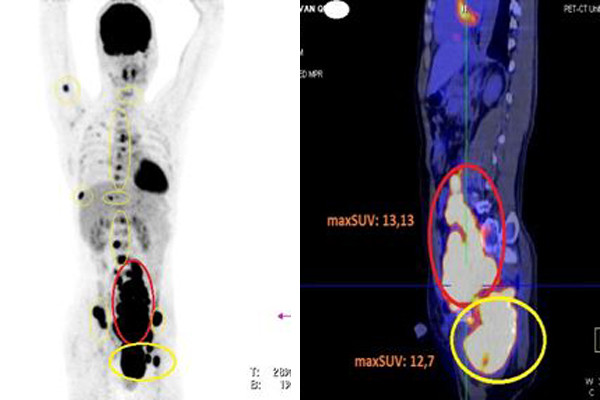

| Hình ảnh PET/CT cho thấy bệnh nhân có nhiều hạch khắp cơ thể, các hạch tăng hấp thu FDG (vòng tròn màu đỏ), các tổn thương xương tăng hấp thu FDG (vòng tròn màu vàng) |

Tiếp tục chỉ định chụp PET/CT toàn thân để đánh giá các tổn thương và giai đoạn bệnh, bác sĩ phát hiện ổ bụng có rất nhiều hạch dọc cơ thắt lưng chậu, hạch hố chậu trái, nhiều hạch bẹn trái, hạch kích thước lớn nhất tương đương quả trứng gà.

Ngoài ra, bệnh nhân có nhiều ổ tổn thương ở xương sọ, đốt sống cổ C2, các đốt sống ngực D4, D5, D7, D8, D12; các đốt sống thắt lưng L2, L4; xương cùng S1; xương cánh chậu phải, tủy xương cánh tay phải; xương sườn số 9; xương đòn phải; xương ức; tổn thương xương chậu trái có khối xâm lấn cổ xương đùi trái và phần mềm xung quanh, kích thước 13,3x8,1 cm.

GS Khoa cho biết, với kết quả như trên, bệnh nhân đã mắc ung thư u lymphoma ác tính không Hodgkin tế bào B giai đoạn 4. Do tế bào ác tính đã lan nhiều khu vực, bác sĩ chỉ định bệnh nhân dùng hoá chất kết hợp kháng thể đơn dòng Rituximab; thuốc chống hủy xương kết hợp thuốc giảm đau, nâng cao thể trạng.